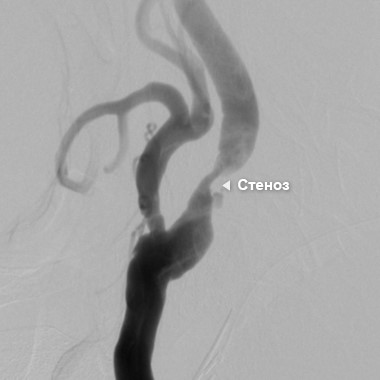

Цифровая Субтракционная Ангиография

Ангиография — это метод исследования кровеносных сосудов различных органов (мозга, сердца, лёгких, почек и др.) с введением в них контрастного вещества. Эти безвредные для организма специальные вещества позволяют увидеть сосуды под рентгеном. Данный метод обследования существует уже более 80 лет и при этом до сих пор остается «золотым стандартом» в диагностике поражений сосудов. Ангиография позволяет ответить на все вопросы, относящиеся к поражению артерий. Единственный «минус» исследования — необходимость пункции (прокола) артерии. Как правило, для диагностики состояния сосудов шеи, в том числе сонных артерий, выполняется пункция либо лучевой артерии на правом запястье, либо общей бедренной артерии в зоне паховой складки. Первый способ более комфортен для пациента, т.к. не ограничивает его в движениях по палате или больнице, в то время как после пункции бедренной артерии требуется строгий постельный режим в течение не менее 6 часов для профилактики кровотечения.

Сужение (стеноз) в сонной артерии, образовавшееся за счет атеросклеротической бляшки. Вид при ангиографии

За четыре часа до ангиографии нельзя принимать пищу. Пациент укладывается на ангиографический стол. В артерию под местным обезболиванием вводится специальный катетер, через который вводиться контрастное вещество. Все действия внутри сосуда контролируются с помощью рентгенотелевидения. Врач в режиме реального времени отслеживает прохождение окрашенной контрастным веществом крови по артерии и выявляет возможные проблемы, связанные с состоянием сосудов. Это позволяет поставить самый точный диагноз, так как катетер подводится врачом непосредственно к интересующей артерии.

Значимое сужение артерии — сужение, которое существенно снижает уровень кровотока. Как правило, это сужение более 70–75% от общего диаметра артерии. При этом врач должен также учитывать и структуру самой атеросклеротической бляшки, которая может не приводить к значимому сужению, но быть опасной в плане миграции своих частиц в сосуды головного мозга.